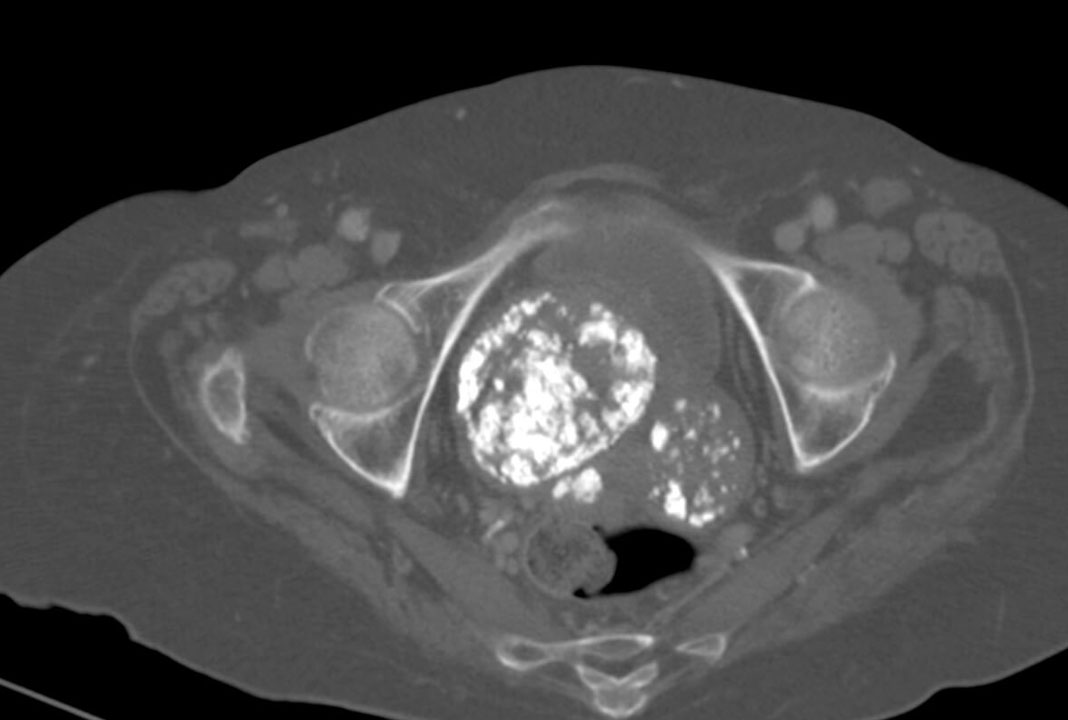

U nang buồng trứng là hiện tượng xuất hiện một tập hợp tế bào trên buồng trứng của phụ nữ trước hoặc trong kì mang thai. U nang buồng trứng thường phát sinh từ một nhóm bất kì trong cơ thể, thường là từ buồng trứng hoặc các cơ quan lân cận. Thông thường, loại u này khá lành tính, tuy nhiên trong nhiều trường hợp có thể phát sinh biến chứng, cần cắt bỏ hoặc có phương án xử lý trước khi u xâm hại tới cơ thể.

Trong số các bệnh phụ khoa thì u nang buồng trứng là loại bệnh thường gặp, chiếm khoảng gần 4% tỉ lệ. Thời gian đầu, u tăng trưởng chậm và không gây hại, nhưng khi phát sinh tác động ác tính thì u lại thể hiện triệu chứng rất nhanh.